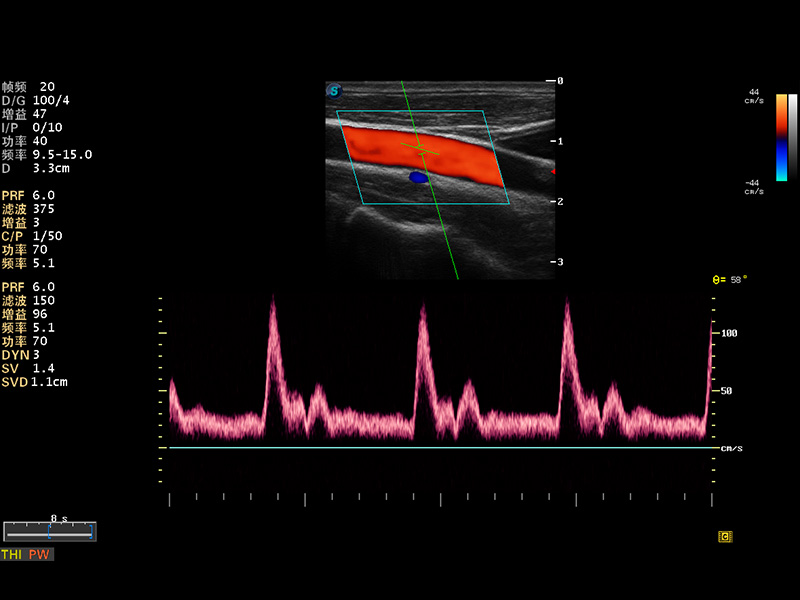

S8 EXP便携式彩色多普勒超声诊断仪是银河集团官网研发的高端全身应用型便携彩超。高通道的VIS平台融合可视化(Visual)、智能化(Intelligent)和人性化(Smart)的特点,配以银河集团官网自主研发生产的探头大家族,使您能够快速、准确的获得病人信息,提高工作效率的同时减轻疲劳。

μ-Scan微米成像